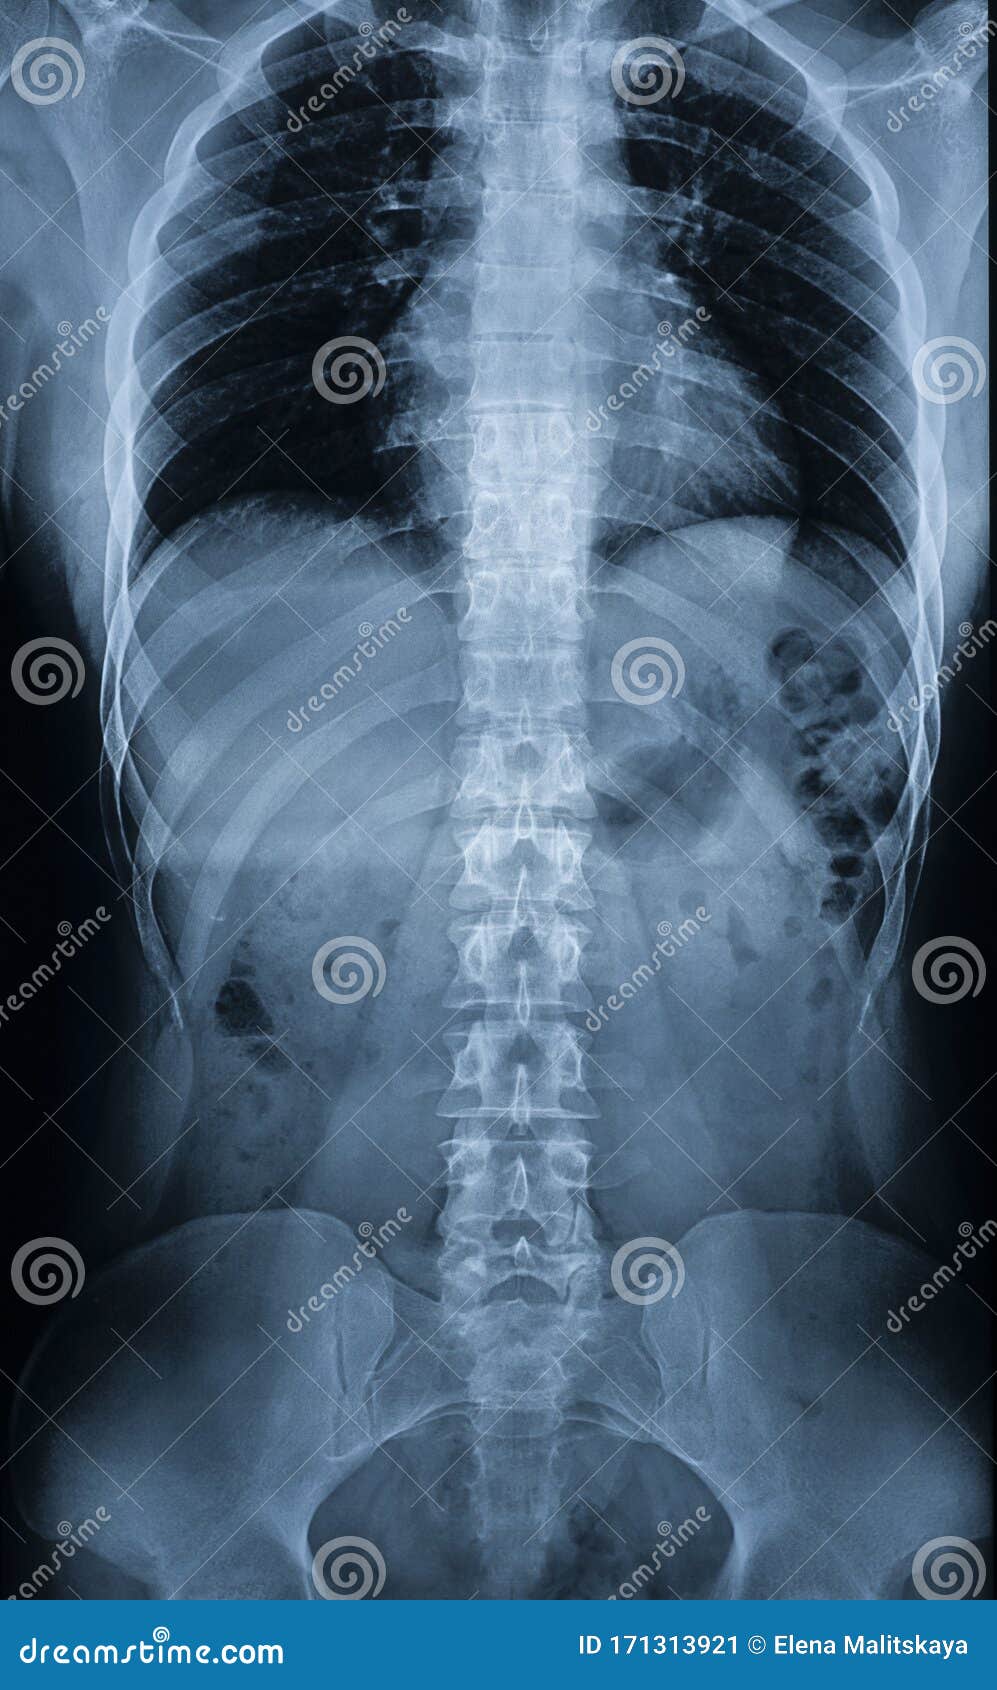

Rayos X Del Cuerpo De Un Hombre - Columna Vertebral, Huesos Pélvicos

es.dreamstime.com

es.dreamstime.com